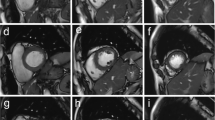

The structure visualization assessment of the end-systolic and end-diastolic images using cine MRI and RT-MRI were rated good to excellent on average. Images with poor quality and images in which the structures were not visible did not occur (Fig. 2).

Image quality analysis. a, b Real time and conventional MR images in short axis orientation. a Standard cine images (conventional cine balanced SSFP sequence, planes 6 and 9) and RT images (RT balanced SSFP sequence, planes 6 and 9) of 7-, 14- and 16-year-old patients no. 4, 12, 18, (female, male, male), were rated good = 3 and excellent = 4 on average for structure visualization based on established 4-point scales [13, 15]. b The most common artifacts were metallic artifacts (e.g., sternal clips) (arrows), which affected standard cine MRI significantly more often and more severely than RT-MRI. Images of 11-year-old patient no. 9 (female). Respiratory artifacts (stars) occurred more often with cine MRI whereas RT-MRI was not affected by respiratory ghosting. Images of 5-year-old patient no. 19 (female). MRI magnetic resonance imaging, RT real-time, RT-MRI real-time magnetic resonance imaging, SSFP steady-state free precession

Cine images were slightly superior to RT images in most structural visualization categories, especially in patients with good breath hold (Table 3 and supporting video in Online Supplementary Material 1, Part 1). Minor differences were seen in LV/RV endocardial borders (cine: 3.7 ± 0.4; RT: 3.5 ± 0.5), epicardial borders (cine: 3.7 + /0.4; RT: 3.5 ± 0.5) and myocardium (cine: 3.8 ± 0.3; RT: 3.6 ± 0.5). Cardiac motion showed no difference between both techniques (cine: 3.9 ± 0.2; RT: 3.9 ± 0.2). Whereas especially the visualization of the papillary muscles (cine: 3.9 0.2; RT: 3.5 ± 0.5) and the blood pool contrast (cine: 3.9 ± 0.3; RT: 3.5 ± 0.5) showed better visualization on the cine images. Wilcoxon sum rank test proved the differences in the visualization of the papillary muscles and the blood pool contrast statistically significant (papillary muscles: P < 0.01; blood pool contrast: P = 0.02). RT-MRI was superior in image quality, especially in young patients with breath holding problems (Fig. 3 and supporting video in Online Supplementary Material 1, Part 2).

Artifact rating (European cardiac MR registry)

The two most prevalent artifacts were metallic artifacts and respiratory ghosting, whereas wrap-around, cardiac ghosting, blurring/miss-triggering, and shimming artifacts were rare on standard cine and RT images (Fig. 2).

While cine images, especially in younger patients often showed respiratory artifacts on multiple slices (1.5 ± 1.4), respiratory artifacts did not occur in RT-MRI (0.0 ± 0.0). Wilcoxon rank sum test proved the increased incidence of respiratory ghosting on cine MRI statistically significant (P < 0.01).

Metallic artifacts from sternal wires, Contegra conduits and coils from occlusion of patent ductus arteriosus occurred on RT images (1.2 ± 1.3) and cine images (1.8 ± 1.4) but showed a significantly higher artifact extent on the cine images (P < 0.01) (Fig. 2 and supporting video in Online Supplementary Material 2).

The overall evaluation of the artifact rating demonstrated that RT images were significantly less affected by artifacts than cine images (cine: 0.5 ± 0.4; RT: 0.2 ± 0.2; P < 0.01).